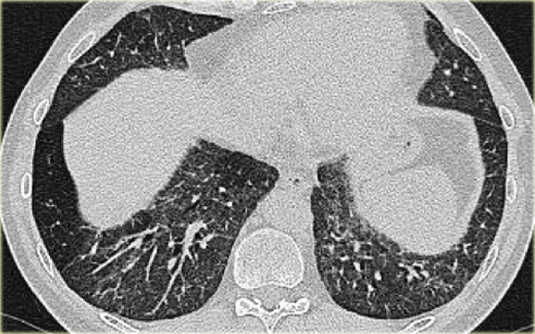

Đây là một trường hợp sarcoidosis phế nang.

Hãy cuộn qua các hình ảnh.

Hình ảnh trông giống như tăng tỷ trọng dạng kính mờ, nhưng khi quan sát kỹ hơn có thể nhận thấy rằng sự tăng tỷ trọng này là kết quả của nhiều nốt nhỏ tập hợp lại.

Cũng lưu ý hạch to rốn phổi.

Sarcoidosis phế nang (2)

Bên trái là bệnh nhân nữ 47 tuổi với triệu chứng ho khan, khó thở nhẹ và xét nghiệm máu bình thường.

Bệnh nhân được chụp X-quang ngực và điều trị kháng sinh.

Phim kiểm tra được chụp lại do bệnh nhân không cải thiện.

Phim X-quang ngực đầu tiên cho thấy đông đặc hai bên ở thùy dưới (mũi tên), ban đầu được diễn giải là nhiễm trùng.

Sau hai tuần điều trị kháng sinh, không có cải thiện.

Chẩn đoán phân biệt lúc này bao gồm u ác tính (ung thư phế quản phế nang hoặc u lympho), viêm phổi tăng bạch cầu ái toan, viêm phổi tổ chức hóa, bệnh Wegener hoặc một thể không điển hình của sarcoidosis.

Tiếp tục với hình ảnh HRCT.

Hãy cuộn qua các hình ảnh bên trái.

Có nhiều vùng đông đặc.

Các dấu hiệu kèm theo bao gồm hạch to rốn phổi và trung thất.

Chẩn đoán phân biệt trên hình ảnh CT về cơ bản giống như trên X-quang ngực.

Kết quả mô bệnh học xác nhận sarcoidosis phế nang.

Chỉ có một gợi ý duy nhất cho chẩn đoán, đó là sự hiện diện của các nốt nhỏ có thể nhận thấy ở hình 3, nhưng rất khó quan sát.

Trường hợp này minh họa rõ ràng rằng sarcoidosis thực sự là “kẻ bắt chước vĩ đại”.

Do đó, sarcoidosis cần được đưa vào danh sách chẩn đoán phân biệt của chúng ta!